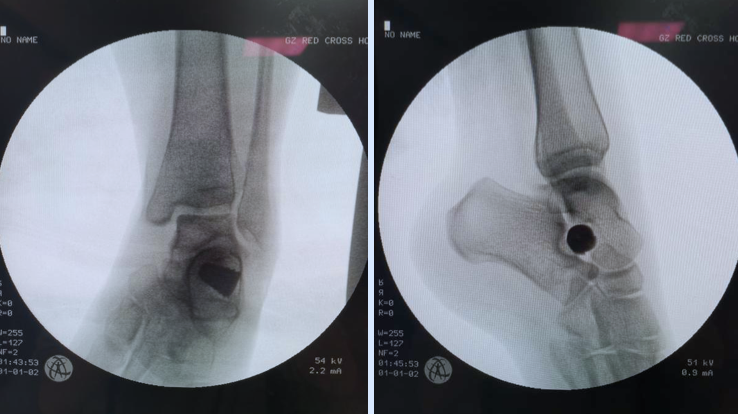

专家根据对患者的检查结果斟酌治疗方案,最后决定采用距下关节制动,增加后足外侧柱高度的微创手术,通过植入距下关节稳定器帮助患者重建足部力线与足弓。孟庆奇副主任医师说,这一治疗方式创口较小,愈合短,术后恢复快,且手术不影响足部各关节完整性,患者实施手术后当天即可下地行走。

患者植入距骨下稳定器后的影像